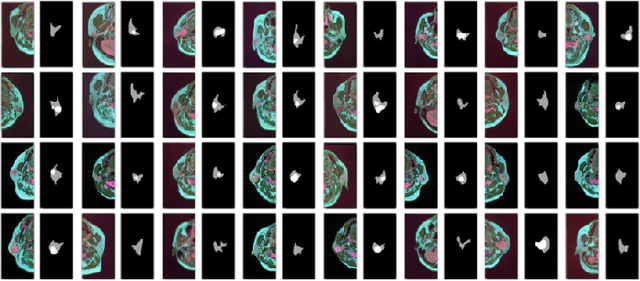

Abstract:Compared with natural images, medical images are difficult to acquire and costly to label. Contrastive learning, as an unsupervised learning method, can more effectively utilize unlabeled medical images. In this paper, we used a Transformer-based contrastive learning method and innovatively trained the contrastive learning network with transfer learning. Then, the output model was transferred to the downstream parotid segmentation task, which improved the performance of the parotid segmentation model on the test set. The improved DSC was 89.60%, MPA was 99.36%, MIoU was 85.11%, and HD was 2.98. All four metrics showed significant improvement compared to the results of using a supervised learning model as a pre-trained model for the parotid segmentation network. In addition, we found that the improvement of the segmentation network by the contrastive learning model was mainly in the encoder part, so this paper also tried to build a contrastive learning network for the decoder part and discussed the problems encountered in the process of building.